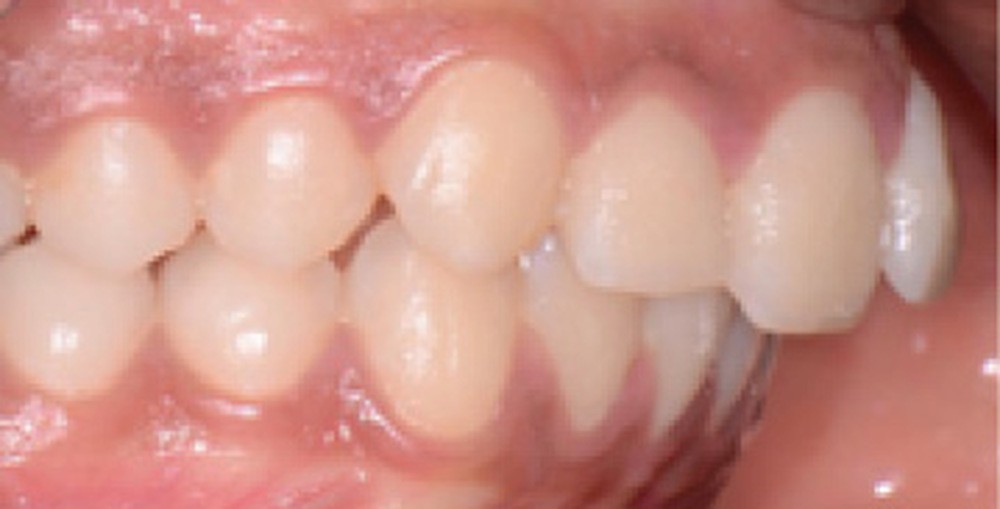

Le résultat de fin de traitement est satisfaisant. Le profil de la patiente est harmonisé. Une contention fixe mandibulaire et maxillaire de canine à canine est choisie.

À propos du cas, on note la persistance d’une petite classe II squelettique (ANB = 5°). Cependant, l’axe de l’incisive maxillaire ne permet pas une correction plus importante de la classe II par avancée mandibulaire car le surplomb est déjà faible et l’incisive maxillaire est légèrement versée (106°). Les axes de 11 et 12 auraient pu être améliorés.